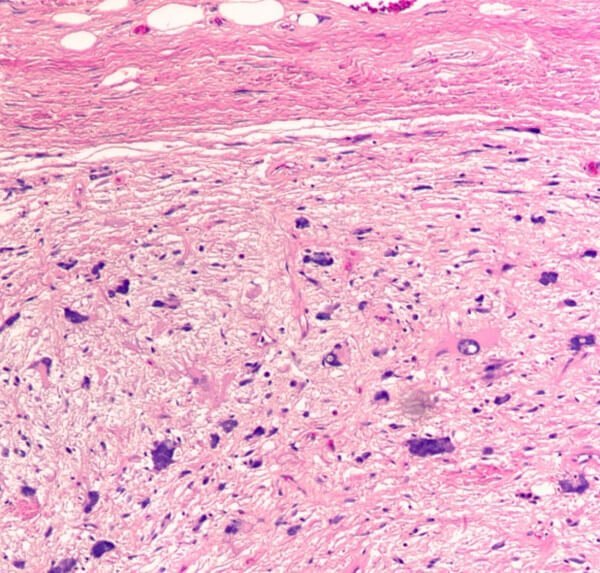

Picture 3 : Intradermal spindle cell lipoma

Image source : surgicalpathologyatlas.com